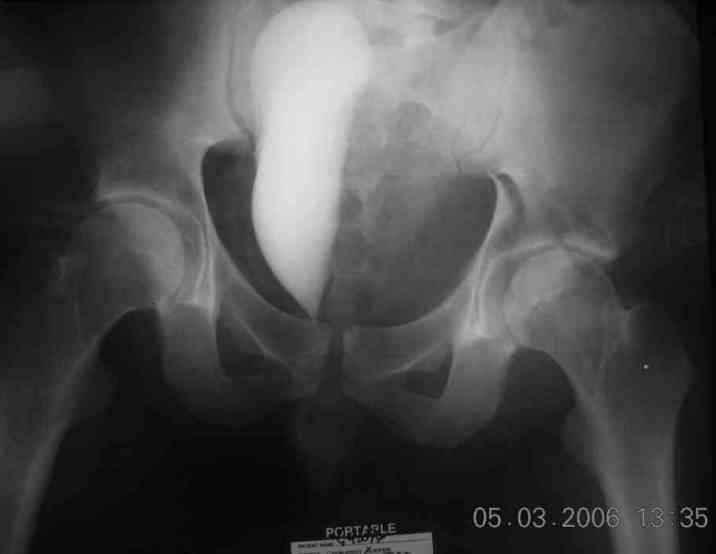

the case that I found is a 20yo male, MCC. his AP pelvis shows an interesting position of his bladder. it is pushed aside by a hematoma from SGA injury. we did a limited lateral window approach for the anterior column first, pt bumped up/supine. then closed and repositioned for KL. I could not find intra-op photos of cases when we did only a small incision for the AC screw (but they do exist!!). the lateral window is available for reduction assessment if a KL approach is being used. in the lateral position this window is available. the prone position definitely takes pressure off of the post column and facilitates reduction. in the lateral position a schantz pin in the ischial tub +/- bone hook in sciatic notch helps with PC reduction. the lateral position also gives better airway access for anesthesia. airway problems are rare, but prone position seems to be a bit more of a challenge to exchange the tube, or reintubate altogether. just something further to debate!